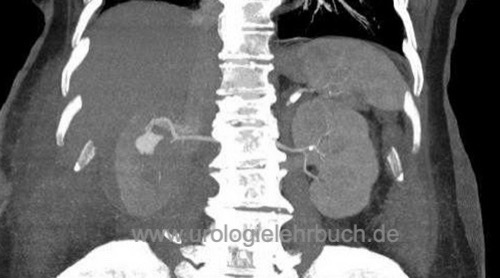

Die offen-chirurgische Nierenteilresektion ist die Standardtechnik für organerhaltende Resektion von Nierentumoren (wie dem Nierenzellkarzinom). Minimalinvasive Alternativen sind die (roboter-assistierte) laparoskopische oder retroperitoneoskopische Nierenteilresektion (Novick, 2002).

Die S3-Leitlinie gibt der Nierenteilresektion bei lokalisiertem Nierenzellkarzinom eindeutig den Vorzug. Falls technisch möglich, soll bei T1-Tumoren und sollte bei T2-Tumoren eine Nierenteilresektion anstatt einer Tumornephrektomie durchgeführt werden. Retrospektive Vergleiche zwischen Tumornephrektomie und Nierenteilresektion bei T1-Tumoren zeigten eine bessere Prognose für die Nierenteilresektion. Dies wird mit einer Reduktion kardiovaskulärer Erkrankungen durch die bessere Nierenfunktion erklärt (Zini, 2009) (Weight, 2010). Die randomisierte EORTC-Studie (Tumornephrektomie vs. Nierenteilresektion) konnte diesen Effekt nicht nachweisen (Van Poppel u.a., 2011).